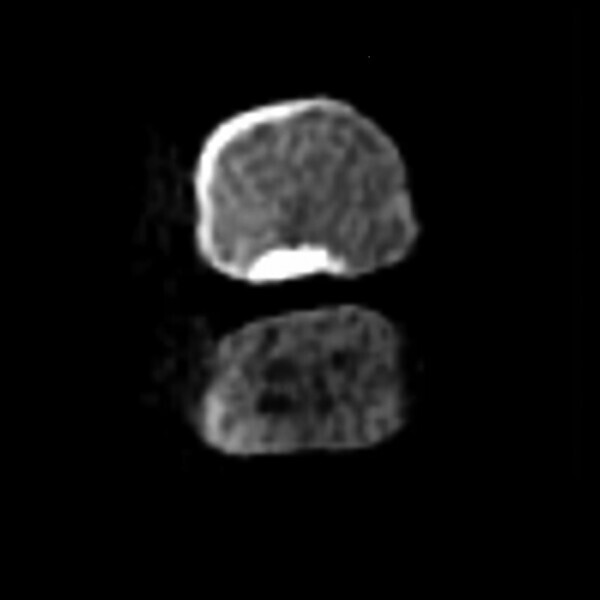

J’ai décidé d’utiliser le système d’imagerie i-CAT, afin de mieux comprendre ce qui se passait. Par comparaison avec la cavité pulpaire de la première molaire, l’examen de la coupe dans le plan horizontal a clairement montré la présence d’une calcification pulpaire de la deuxième molaire (Fig. 2).

Le mode endodontique du nouveau logiciel DTX Studio Clinic permet d’ajouter de nombreuses vues et coupes transversales, ainsi que d’ajuster l’épaisseur des coupes pour vérifier le degré de calcification. Un autre avantage est la possibilité de tracer l’anatomie interne de chacune des racines et de l’ensemble du système, et de sélectionner une couleur pour chaque canal. Cette option est très utile pour examiner l’anatomie interne (Fig. 3).